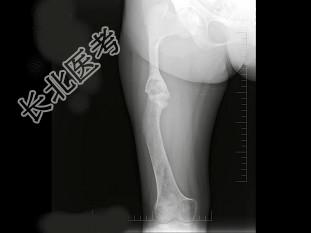

- 单项选择题男,17岁, 下肢畸形,有皮肤色素沉着, 性早熟等,结合图像, 最可能的诊断是 ( )

C、骨纤维结构不良